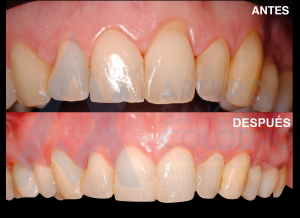

Los tecnicismos puede que no os digan mucho, pero dejamos por aquí unas fotos del antes y el después en las que puede apreciarse la mejoría del caso:

ANTES/DESPUÉS